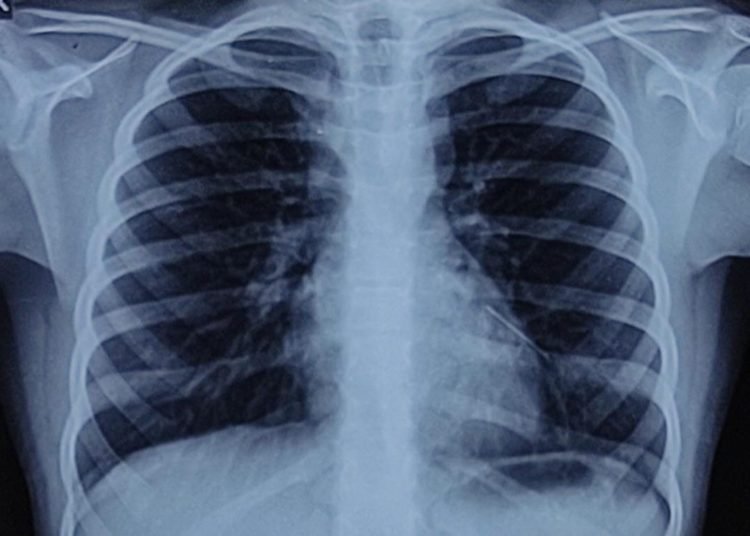

About two years ago, Naira Shah (name changed), a 10 –year-old girl from Mumbai accidentally swallowed a metallic pin. An x-ray of the abdomen was done and it failed to reveal the foreign body and everybody eventually forgot about the incident. Her life was smooth until the patient started complaining of dry cough after 1.5 years of sleeping in certain positions. Hence, the patient visited Zen Multispeciality Hospital for further investigations.

Dr Kshitij Shah, ENT Surgeon said, “To our utter surprise, an x-ray of the chest revealed a metallic foreign body in the lower airway on the left side. A CT scan of the chest was done to precisely locate the foreign body. After an initial attempt at removal of the foreign body by flexible bronchoscopy, a decision was made to perform a rigid bronchoscopy.”